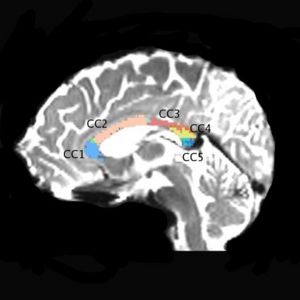

Our objective is to measure differences in fractional anisotropy (FA), trace, mode, and volume of five subdivisions of the corpus callosum of schizophrenic patients vs. normal controls using an automatic clustering method and high resolution 3 Tesla data.

We are using a high resolution 3 Tesla scans, 1.7x1.7x1.7 mm, 51 diffusion directions, 8 baselines (data available to NAMIC investigators). So far we scanned 24 subjects, 12 chronic schizophrenics and 12 matched control subjects. Fiber tractography is performed on the whole brain, and then an automatic clustering method (O’Donnell et al., 2006), is applied. Midsagittal slice is then painted according to anatomical clusters, which results in 5, reliable clusters. Mean FA, mode, trace as well as volume of each clusters are obtained for each subject, and compared between groups.

Preliminary results show a reduced FA in the second cluster (CC2) of the corpus callosum in schizophrenics and a reduced volume in the third cluster (CC3) of schizophrenics, when compared with control subjects.